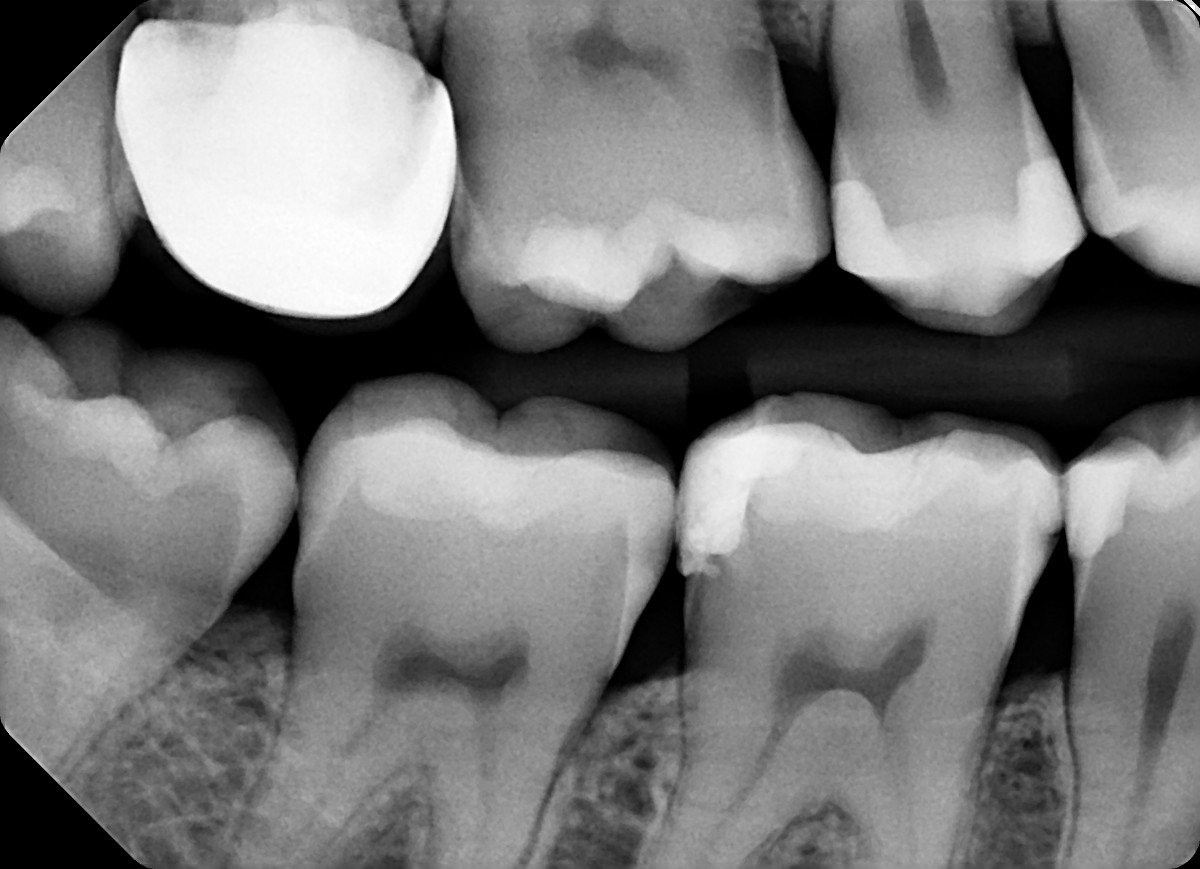

8 / 35

8. On which surface a recurrent caries can be detected?

under crowns the recurrent caries can easily become cavtated ad they are seen more radiolucent